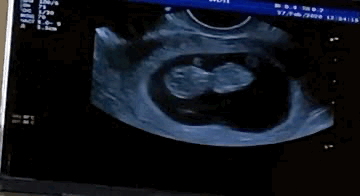

9 недель